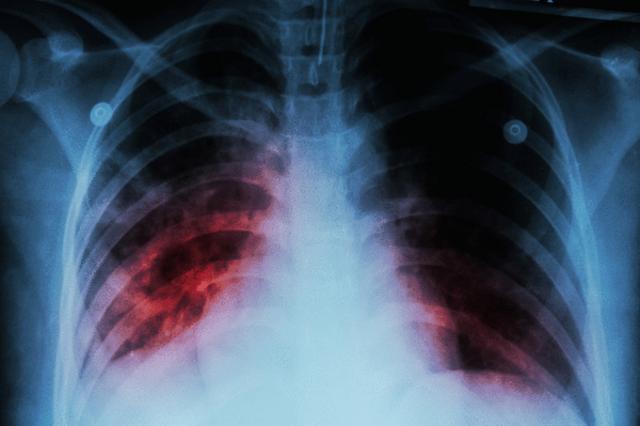

New tuberculosis case detected in Northern California. Here's what to know

After an active case of tuberculosis was detected in the Sacramento area, you may be wondering about your risks of ... Read More